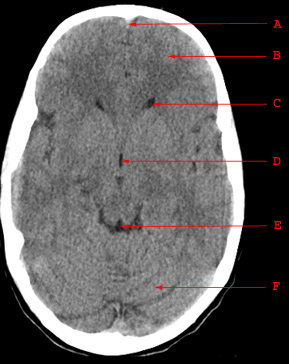

Normal Anatomy

A. Falx Cerebri B. Frontal Lobe C. Anterior Horn of Lateral Ventricle D. Third Ventricle E. Quadrigeminal Plate Cistern F. Cerebellum

A. Falx Cerebri

B. Frontal Lobe

C. Anterior Horn of Lateral Ventricle

D. Third Ventricle

E. Quadrigeminal Plate Cistern

F. Cerebellum